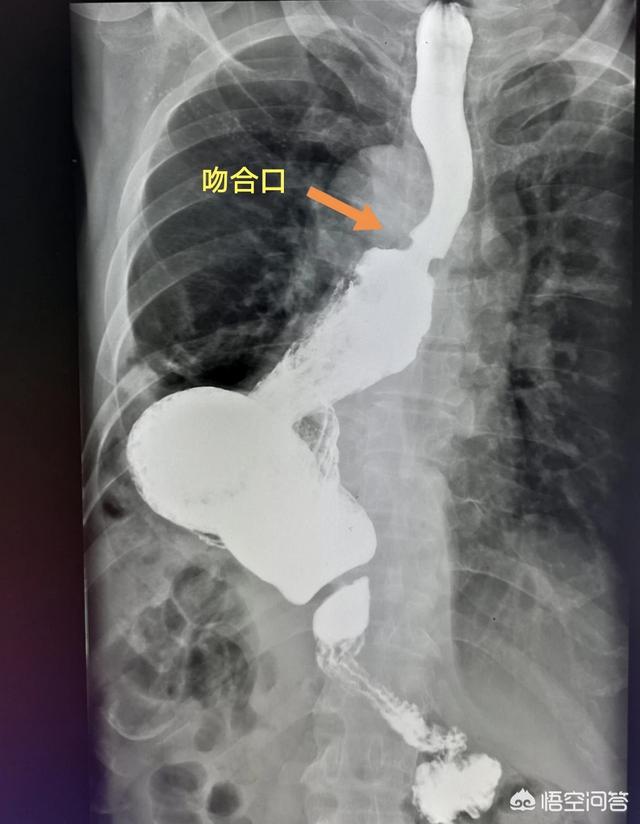

上图就是一位比较早期的食管癌病人。手术成功切除食管中下段。把食管上段和胃吻合。已经八年半了。恢复得很好。